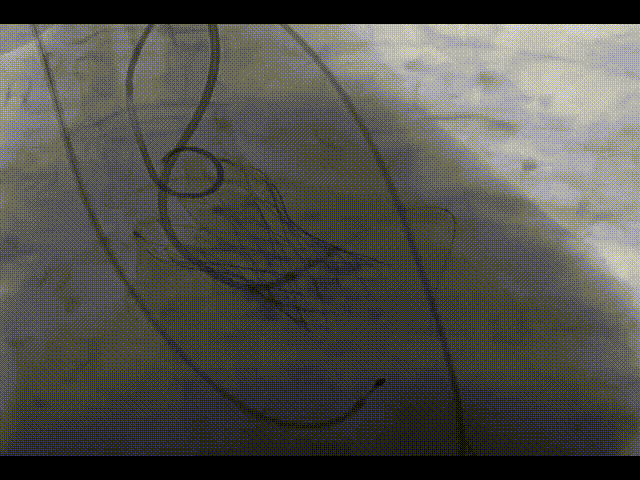

瓣膜完全释放

造影显示瓣膜形态欠佳

超声提示形态及血流动力学欠佳

22mm球囊后扩

造影显示形态显著改善,微量瓣周漏

术后即刻评估

超声评估,形态及血流动力学良好

右足左冠造影,灌注良好